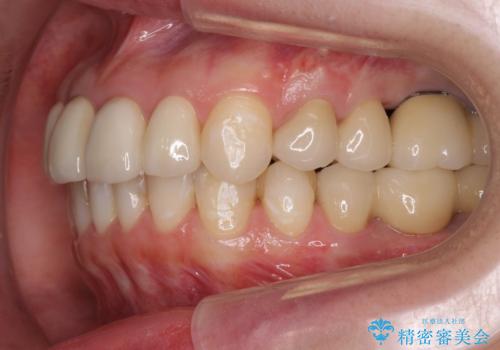

インプラント・セラミック・矯正治療を含む包括歯科診療

- 20代女性

- 矯正装置

- インビザライン

- 治療期間

- 3年

- 治療回数

- 30回以上

- 「地元の歯医者にずっと通っているが、どんどん歯が悪くなる。時間とお金がかかってもいいので徹底的に歯を治したい。」

、と総合的な歯科治療を希望されて来院されました。

虫歯や咬合関係・歯槽骨の吸収・根尖病変・歯の欠損・複合的な問題を一つずつ解決し、

安定した噛み合わせの構築・歯ブラシのしやすい環境の整備・歯内歯周の感染除去・造骨を伴うインプラント治療

を行い、長期的な予後を見込める口腔内環境を確立、整備して行きます。

- 440万円費用は治療当時の料金となります